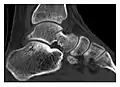

a

b

Figure 6: Subtle anterior talar fracture in a 39-year-old man presenting with ankle pain after a fall. (a) Anteroposterior radiograph shows a subtle oblique radiolucent line through the talus (white arrows). (b) Sagittal CT reformation confirms the presence of an anterior talar fracture with cortical offset (black arrow). Avulsion fractures, which consist of a detached bone fragment resulting from a ligament or tendon pulling away from the bone, may also present with subtle radiographic signs. Tiny osseous fragments near the presumed attachment site of a ligament suggest this diagnosis. Common sites are the lateral tibial plateau (the Segond fracture), the spinal tuberosity of the tibia resulting from anterior cruciate ligament avulsion, and the ischial tuberosity.[1]